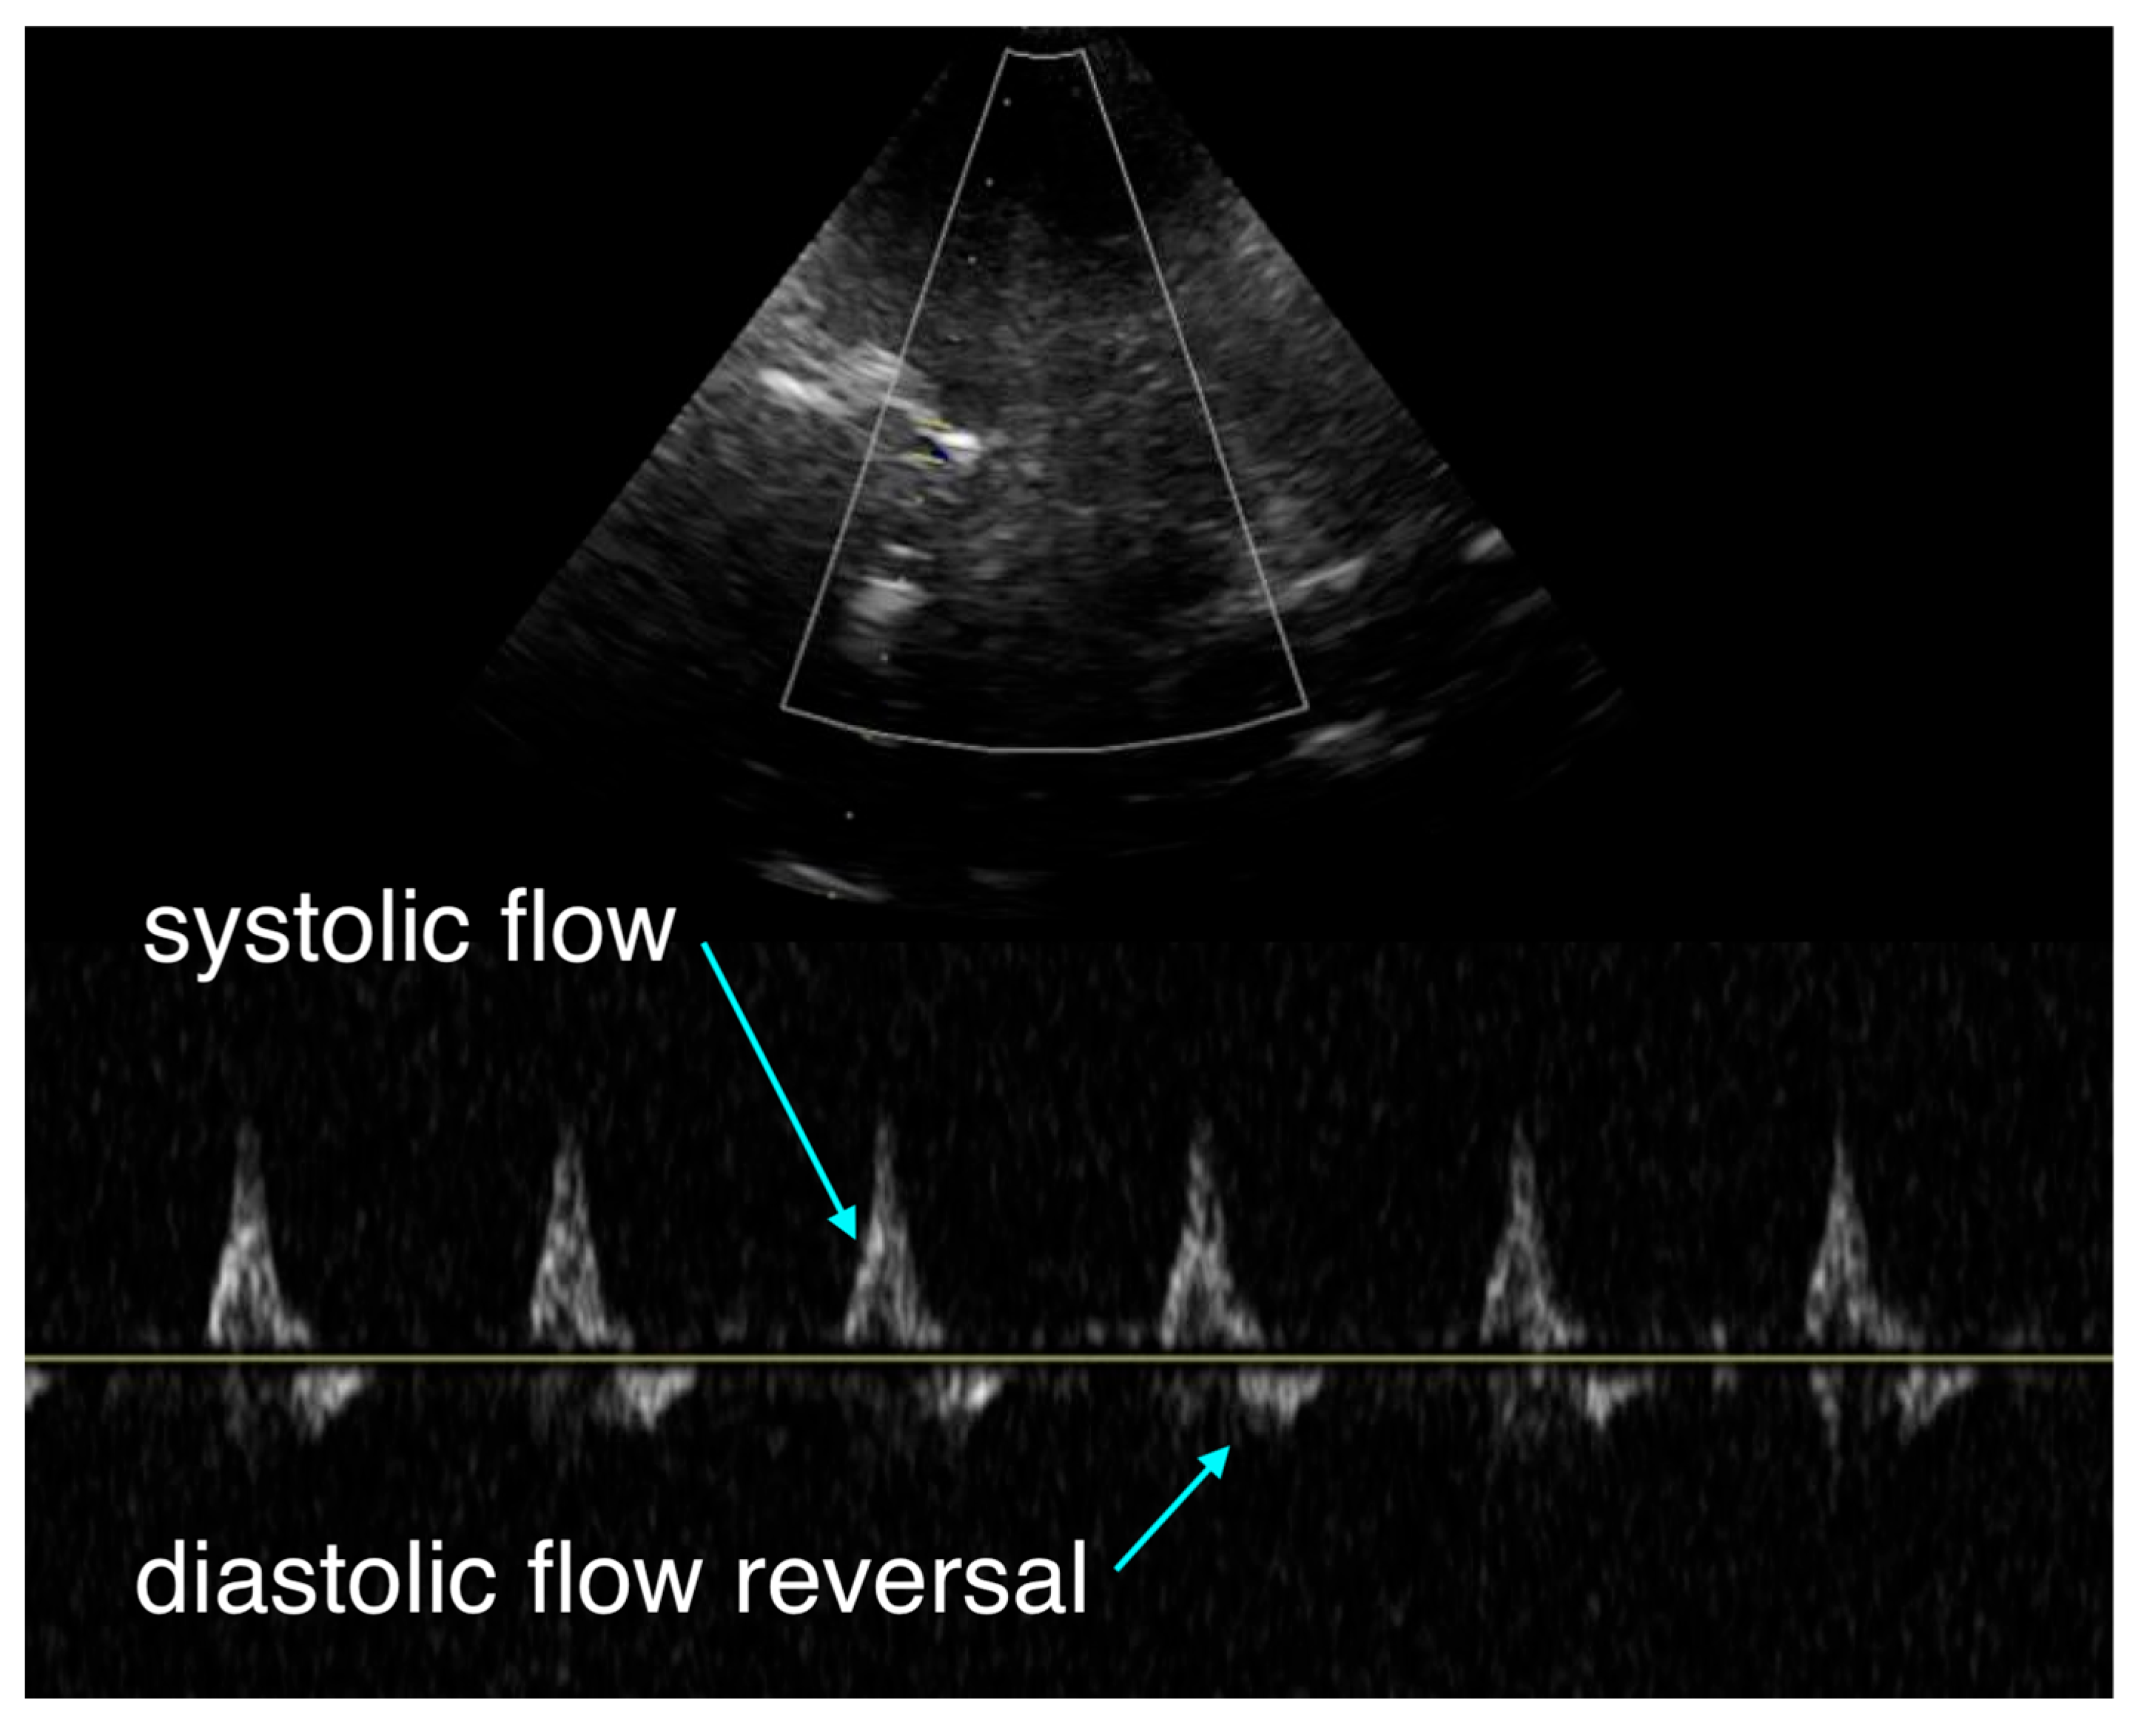

The team initiated transcranial Doppler (TCD) monitoring, which revealed systolic upstroke but diastolic flow reversal and no sustained forward flow during diastole (Figure 1). This pattern suggested either severe cerebral vasoconstriction secondary to catecholamine effect or elevated intracranial pressure beyond diastolic arterial pressure.

Transcranial Doppler (TCD) offers a noninvasive window into cerebral flow during arrest, a domain largely invisible to current monitors. The pattern of antegrade systolic but reversed diastolic flow seen here has been previously described in pediatric arrest literature [1]. This waveform indicates critically impaired downstream flow, consistent with either severe vasoconstriction or markedly elevated intracranial pressure. Within our own conceptual framework of hemodynamic interfaces, this represents uncoupling of interface 2, the arteriolar–capillary interface, where cerebral perfusion is compromised despite adequate proximal pressure [2]. This tool may allow clinicians to differentiate between potentially reversible vasoconstrictive hypoperfusion and irreversible intracranial hypertension, a distinction currently impossible in real time.

Figure 1. Intra-arrest transcranial Doppler (TCD) waveform obtained during mechanical chest compressions. The tracing demonstrates antegrade systolic flow with early diastolic flow reversal and absence of sustained forward diastolic flow, consistent with markedly impaired intracranial perfusion.